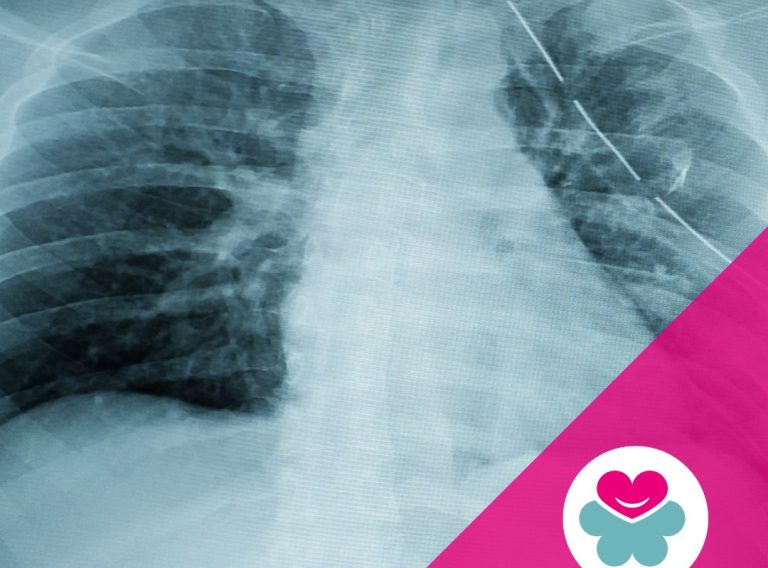

- Riabilitazione post-operatoria, per interventi chirurgici ortopedici o neurologici.

- Patologie degenerative, come artrosi e malattie reumatiche.